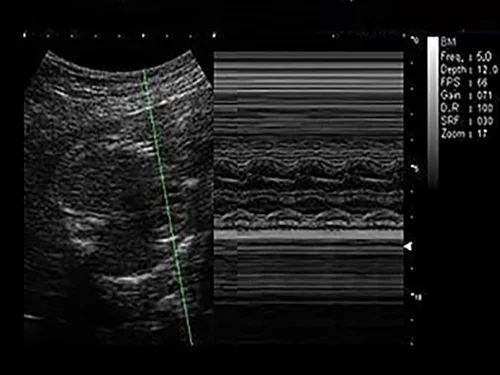

M-режим, анатомический M-режим